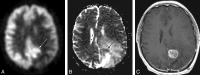

Fig 1.

A 49-year-old man with an anaplastic astrocytoma. The PET scan (A) demonstrates a C-shaped area of increased radiopharmaceutical uptake (arrow), which exquisitely matches the area of restricted diffusion on the ADC map (arrow, B). C, The correspondence between the FDG-PET scan and the ADC map is better than that in the gadolinium-enhanced MR image (C).